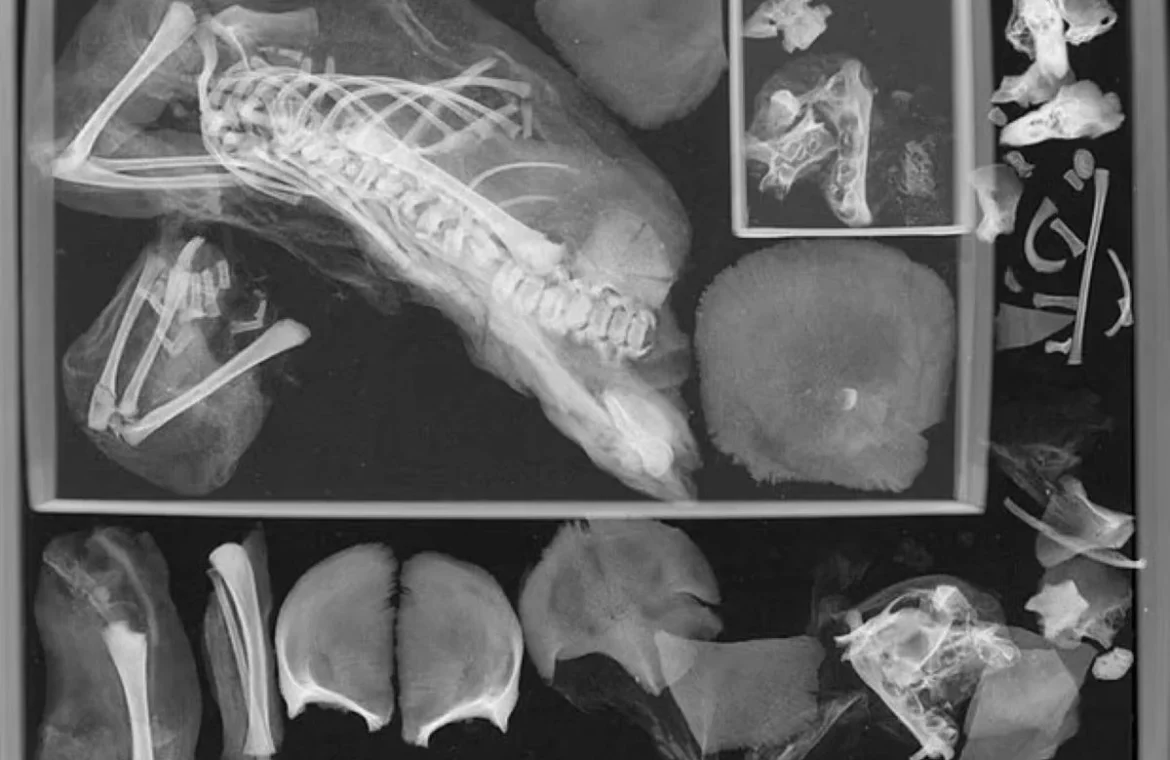

Έναν αιώνα μετά η επιστημονική ομάδα του Πανεπιστημίου George Washington χρησιμοποίησε αξονική τομογραφία (CT) για να διαπιστώσει τι ακριβώς πήγε στραβά στην γέννα. Στην εξέταση αποκαλύφθηκε η παρουσία ενός δεύτερου εμβρύου μέσα στη θωρακική κοιλότητα της έφηβης και αποδείχθηκε ότι κυοφορούσε δίδυμα.

Στην συνέχεια βρήκαν το αποκεφαλισμένο βρέφος ανάμεσα στα πόδια της έφηβης. Μετά από προσεκτική εξέταση είδαν ότι το κεφάλι του μωρού ήταν ακόμη μέσα στην λεκάνη της μητέρας. Έτσι εκτίμησαν ότι το έμβρυο είχε αποκεφαλιστεί κατά τη διαδικασία του τοκετού.

Οι συγγραφείς της μελέτης περιγράφουν ότι το έμβρυο αποκεφαλίστηκε έβγαινε από την μήτρα με τα πόδια πρώτα. «Αυτό είναι ένα σπάνιο εύρημα. Υπάρχουν πολλά παραδείγματα γυναικών που πέθαναν κατά τη διάρκεια του τοκετού στα αρχαιολογικά αρχεία (η μία ήταν δίδυμη εγκυμοσύνη). Ωστόσο, δεν έχει βρεθεί ποτέ στην Αίγυπτο», είπε η Francine Margolis, μια από τις συγγραφείς της μελέτης.

Το δεύτερο έμβρυο που ανακαλύφθηκε στον θώρακα της έφηβης δημιούργησε ερωτήματα. Σύμφωνα με τους ερευνητές, είναι πιθανό ότι οι ταριχευτές δεν γνώριζαν ότι η έφηβη κυοφορούσε δίδυμα και δεν αφαίρεσαν το δεύτερο έμβρυο πριν από τη μουμιοποίηση. Σύμφωνα με το IFL Science, το αγέννητο έμβρυο μπορεί να έχει μετακινηθεί από τη μήτρα στην κοιλότητα του θώρακα καθώς διαλύθηκε το διάφραγμα της μούμιας.